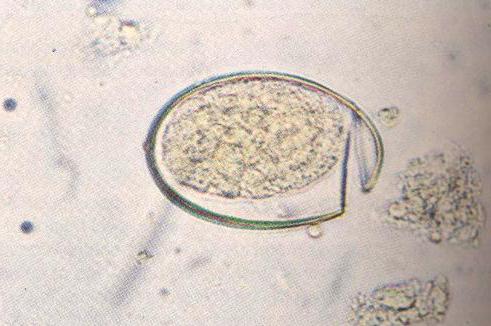

Яйца паразита

Яйца широкого лентеца имеют овальную форму и желтоватый цвет. С одной стороны есть крышечка, через которую выходит личинка. Ежедневно зараженный человек выделяет с фекалиями около миллиона яиц. Но это незрелые формы. Их окончательное развитие происходит в пресных водоемах. Фото яйца под микроскопом представлено ниже.

Часто пациенты интересуются: можно ли самостоятельно обнаружить в кале яйца глиста? Увидеть их невооруженным глазом невозможно, так как они имеют микроскопические размеры. В фекалиях можно обнаружить только выходящие членики, они похожи на ленту белого цвета.